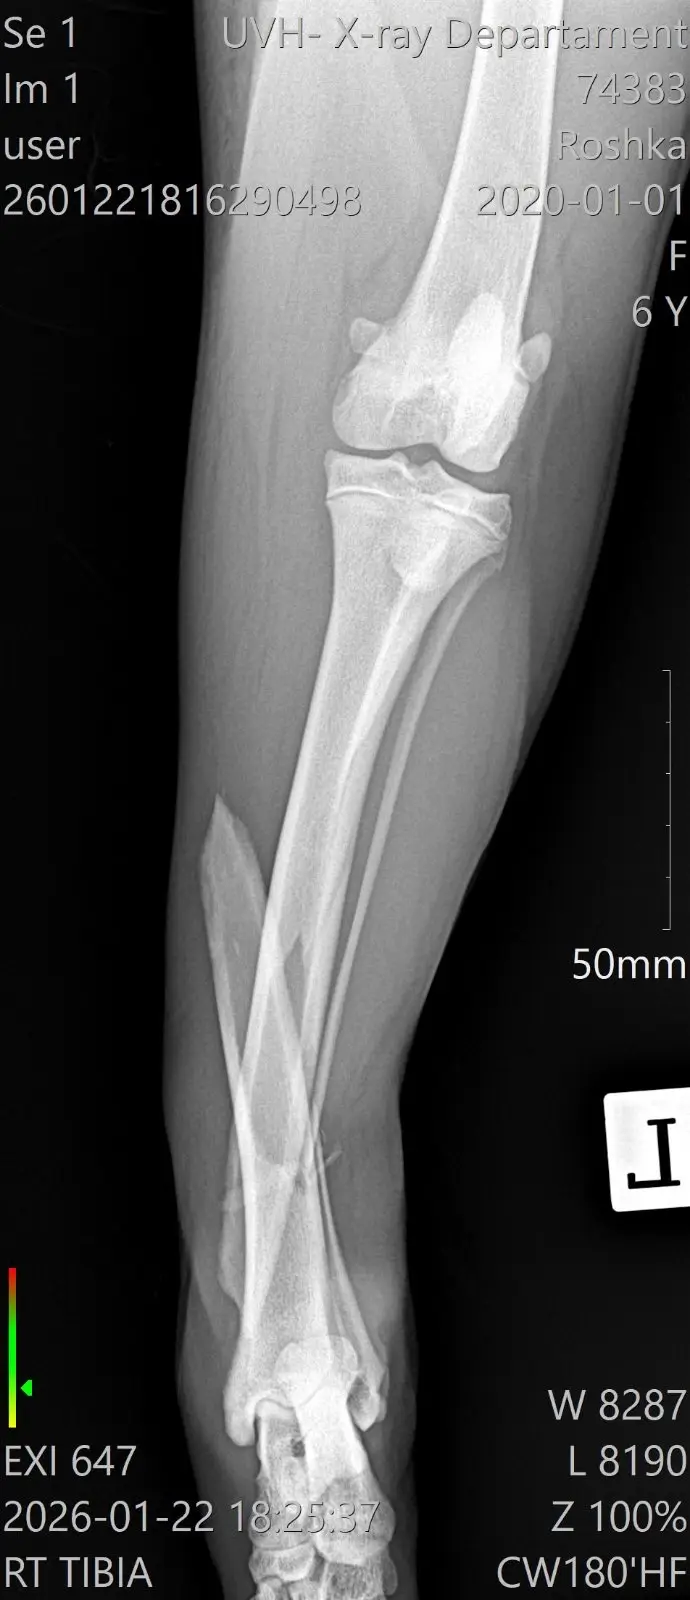

Защо Рошка има нужда от вас

Въпреки силата си, тя не може да се справи сама. Рошка се нуждае от спешни операции на задните краченца. За да може това 25-килограмово тяло да се изправи отново, са необходими импланти и винтове.